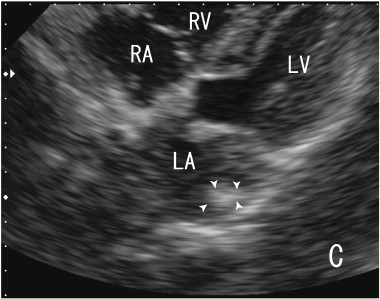

The patient was treated with 100 mg of aspirin without warfarin. The EKG indicated normal sinus rhythm, a normal axis and no ST-T changes, and the patients heart rate was 59 beats/min. A 64-MDCT scan was performed to assess the stenosis of the coronary artery because of recent chest pain. Although the stenosis of the coronary artery was not diagnosed, a large thrombus in LLPV and in LA was noninvasively identified as a defect in enhancements by 64-MDCT scan, which was shown in my previous paper [4]. A pulmonary vein thrombus was identified in LLPV as a defect in contrast enhancements (Fig. 1A and B). The thrombus was visualised using transthoracic echocardiography (TTE) in Fig. 2. In video images using TTE, a thrombus in the LA was demonstrated to be a large bright echodensity, suggesting a thrombus with a highly fibrinous component. The shape of the thrombus in video images was a wavelike, which indicated that the thrombus exhibited flexibility and was rather strong. Some parts of the thrombus attached to the mitral valve were not identified by a 64-MDCT. The volume of the LA was 39 ml, and the patient exhibited no thrombi in the LAA. In this case, TEE can assess the quality and quantity of a left atrial thrombus, but it cannot identify a pulmonary vein thrombus, which is well assessed by a 64-MDCT scan.

Images of transthoracic echocardiography (TTE). The thrombus in the left atrium ...

Fig. 2.

Images of transthoracic echocardiography (TTE). The thrombus in the left atrium (LA) was surrounded by arrowheads, which was located at the posterior wall side in the LA. The echodensity of the thrombi was high, which indicated that the thrombus was fibrous. LA; left atrium, LV; left ventricle, RA; right atrium, RV; right ventricle.